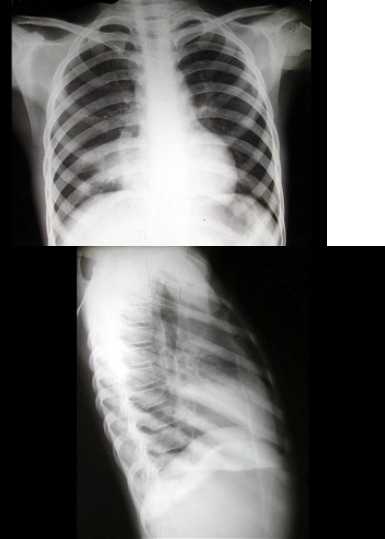

它让医生终于能“纵观全局”了。以前看脊柱侧弯,得靠拍好几张片子在脑子里想象拼接,现在一张全脊柱正侧位片,弯了多少度(Cobb角)、主要弯在哪儿,一目了然-2-7。对于需要做关节置换(比如换膝盖、换髋关节)的病人,术前拍一张双下肢全长拼接片,医生就能精准测量你的下肢力线、关节角度,为安装假体设计出最符合你个人生物力学的方案,这可是手术成功、让假体用得长久的基石-2-9。

它更真实。很多检查可以让你站着拍(立位负重位),这就模拟了你平时走路、承重的真实状态。在这种状态下呈现的脊柱曲度、关节间隙狭窄和畸形,比躺着拍更有诊断价值-7。